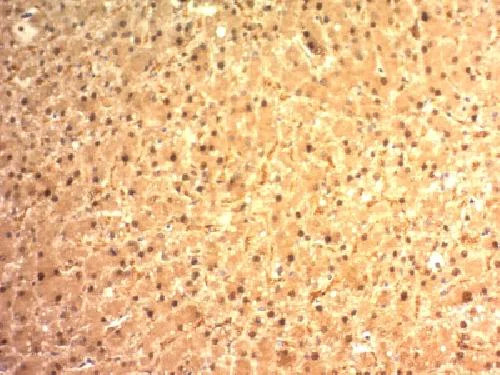

Immunohistochemistry (Formalin/PFA-fixed paraffin-embedded sections) - Anti-Liver Arginase antibody [ARG1/1125] - BSA and Azide free (AB212522)

Immunohistochemical analysis of paraffin embedded Human hepatocellular carcinoma tissue labeling Arginase with ab212522 at 2 μg/mL.